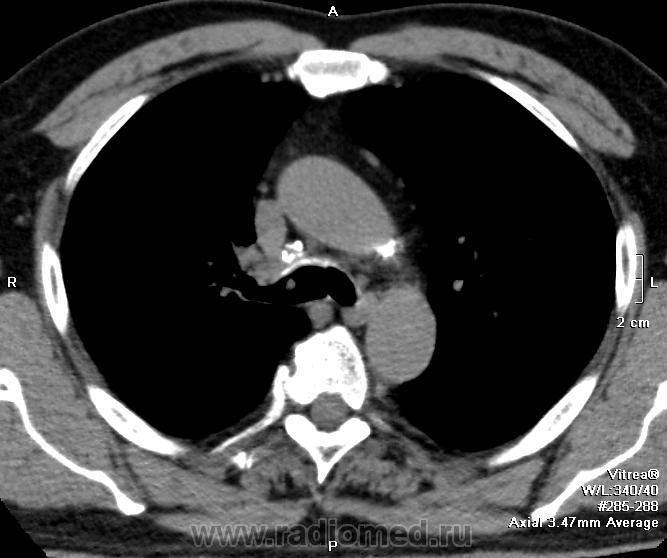

имеющее обсуждение образование одно в области правого главного бронха.. явственно эндобронхиального происхождения.. но что мешает придраться к аксиальным срезам с перитрахеальной ненормальной плотностью?..

Вношу ясность: тут два исследования - первое исследование сделано в понедельник, второе во вторник - в просвете бронха имеет место что то симулирующее tr, что было на верхней стенке, а затем переместилось на нижнюю за сутки - слизь.

теперь, когда коллеги высказали свое мнение и думать стало легче-), спрошу лишь одно по предложенному мной скану - что за циркулярный гитперденсный обхват трахеи (на всех аксиалах)? почему "на ножке"-то?